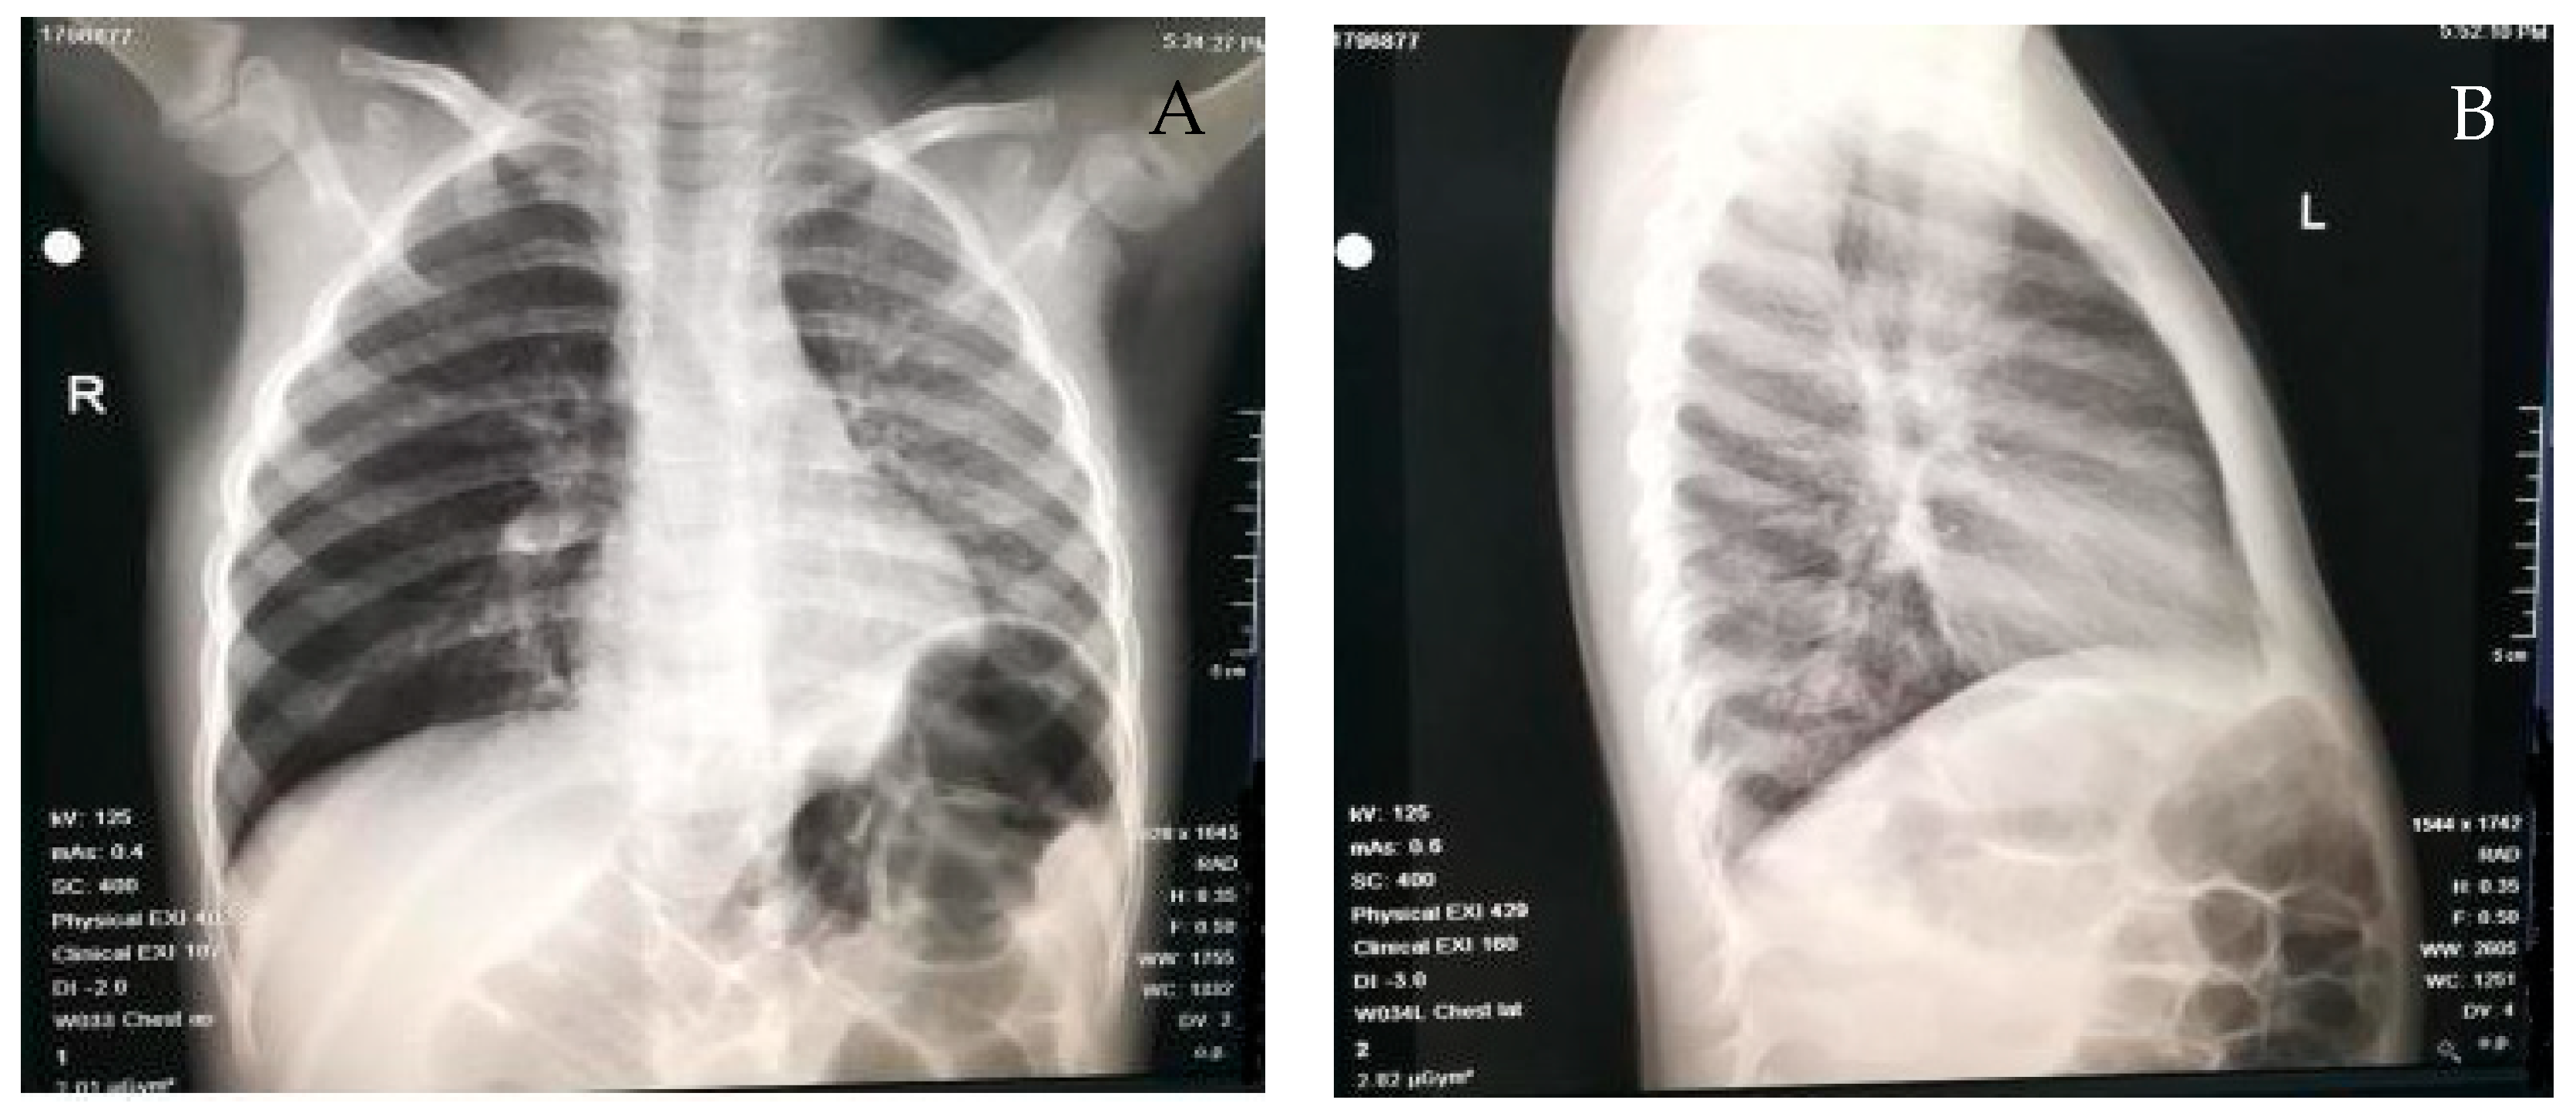

| Chest radiography results | ||

| Pulmonary atelectasis | 62 | 26.85% |

| Pulmonary emphysema | 41 | 17.76% |

| Direct visualization of the foreign body | 8 | 3.44% |